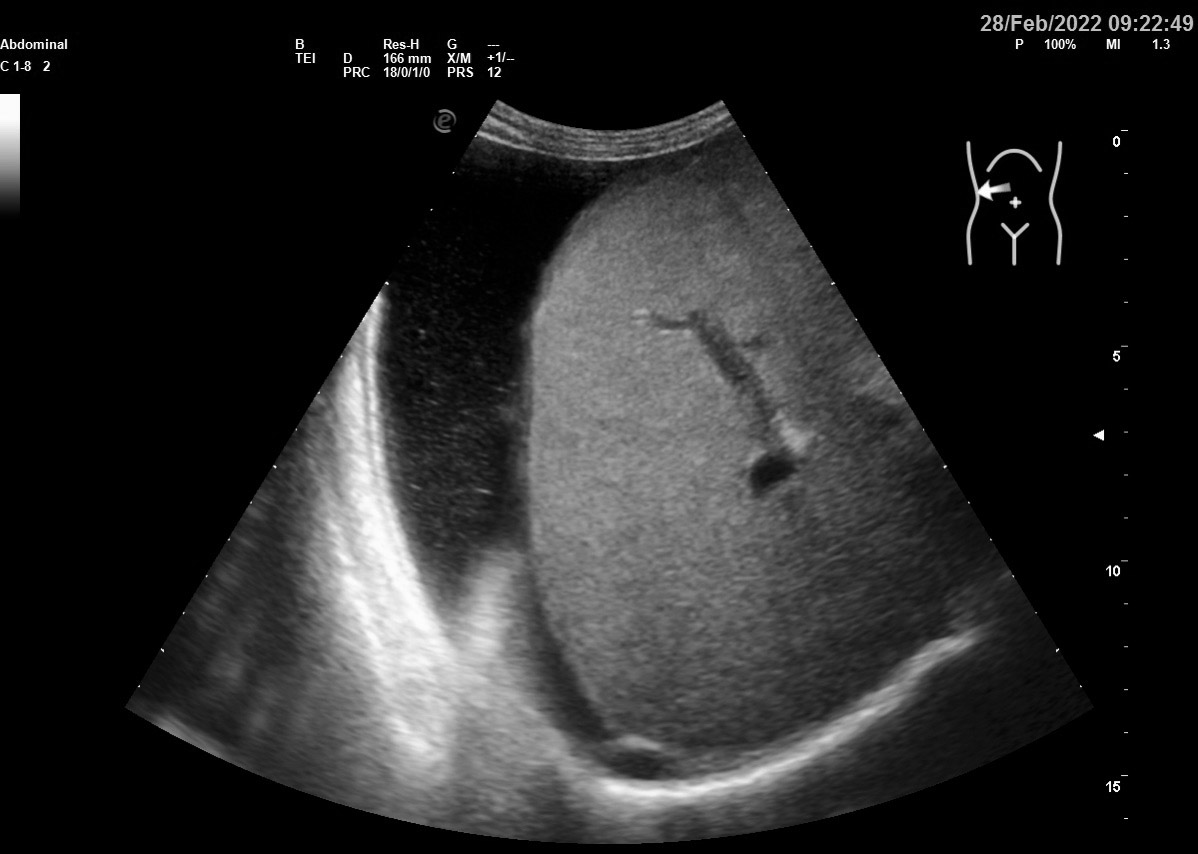

Хирург попросил выполнить разметку для дренирования асцита у женщины. Но что-то заставило рекомендовать КТ.

Что?

Где ЭТО?

Где все ЭТО, характерное для асцита?